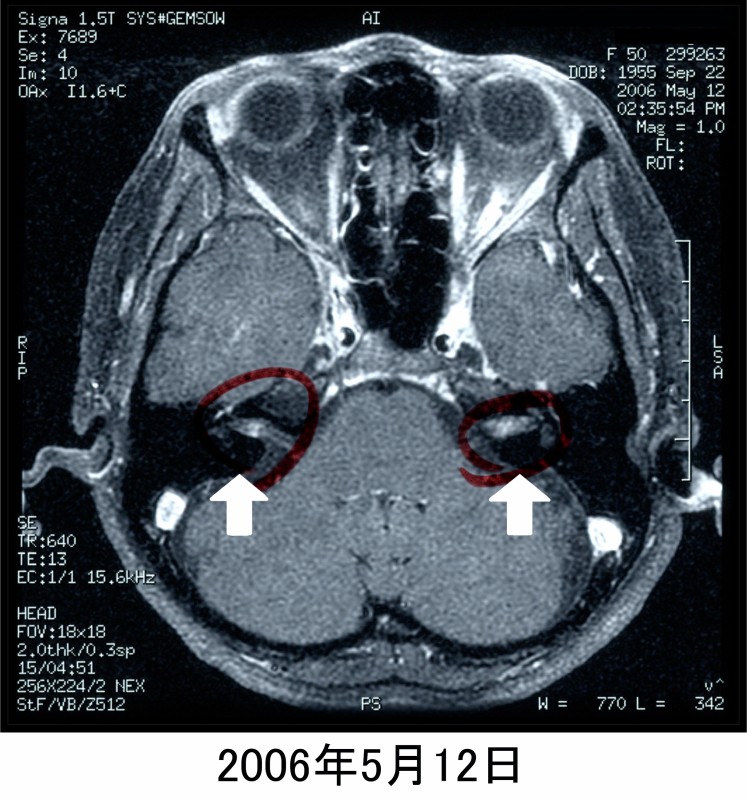

聴力像と眼振所見(図7)です。造影MRI(図8)にて両側内耳道に濃染像を認めます。

受診後3日目となる5月12日にMRIにて両側聴神経腫瘍が発見され、泉病院脳神経科を経て東北大学耳鼻科にて経過観察中となっています。